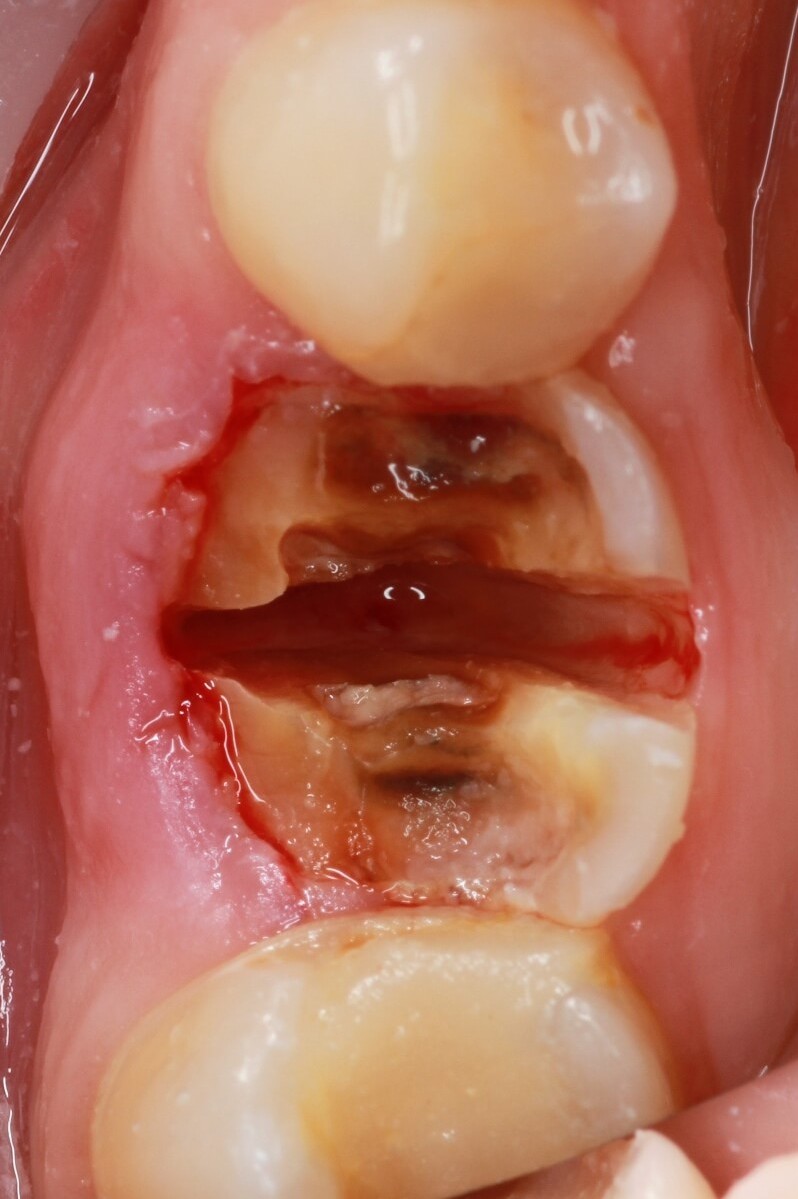

• we remove teeth, agreed in the treatment plan.

• if necessary, we perform bone and gingival grafting

• we install implants

Implantation immediately after careful tooth extraction is the best way to save tissue.